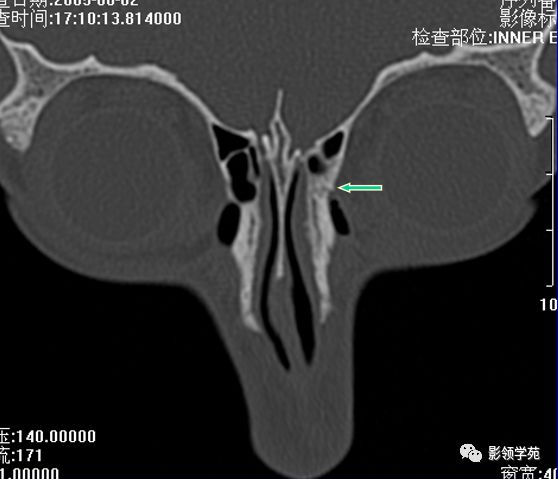

左侧鼻骨线形骨折

右侧鼻骨骨折

左上颌骨额突骨折